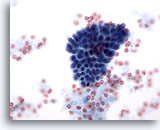

Figure 8

Breast FNA, Fibroadenoma.

In some instances the ductal cell groups have small rounded projections as seen here rather than the long branches noted in the prior two figures. 20x

Figure 8

Breast FNA, Fibroadenoma.

In some instances the ductal cell groups have small rounded projections as seen here rather than the long branches noted in the prior two figures.

20x